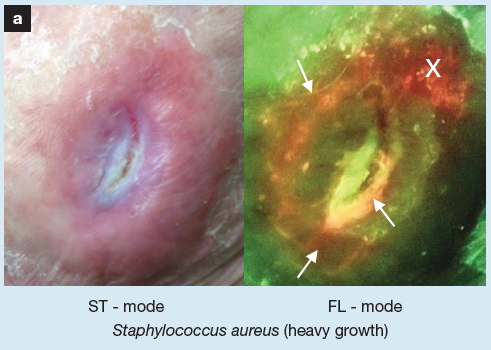

Skin Pigmentation Impacts the Clinical Diagnosis of Wound Infection: Imaging of Bacterial Burden to Overcome Diagnostic Limitations

Johnson J. et al. JREHD 2023

Bacterial Fluorescence Imaging to Address Racial Inequities in Wound Infection Assessment

Andersen, CA et al. Adv Skin & Wound Care 2024